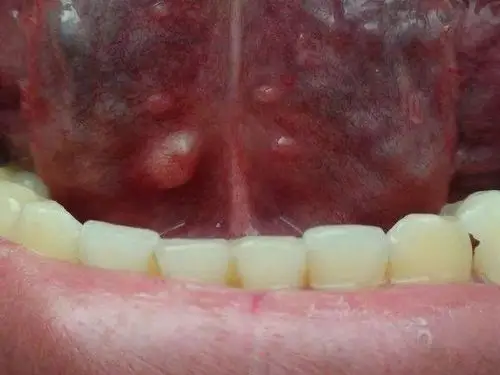

千万别忽视身体这部位的"小疙瘩" 警惕癌变!_肿块